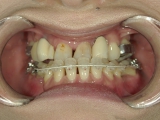

● 臼歯部の後方移動

臼歯を後方に牽引し、移動させることでスペースを確保し歯列を整えます。

抜歯矯正をした経験があり、新たに抜歯

できる歯がないため、臼歯を後方へ牽引

してスペースを確保します。

臼歯にリンガルアーチという装置を装着し、ミニインプラントを固定源に臼歯を後方に牽引します。